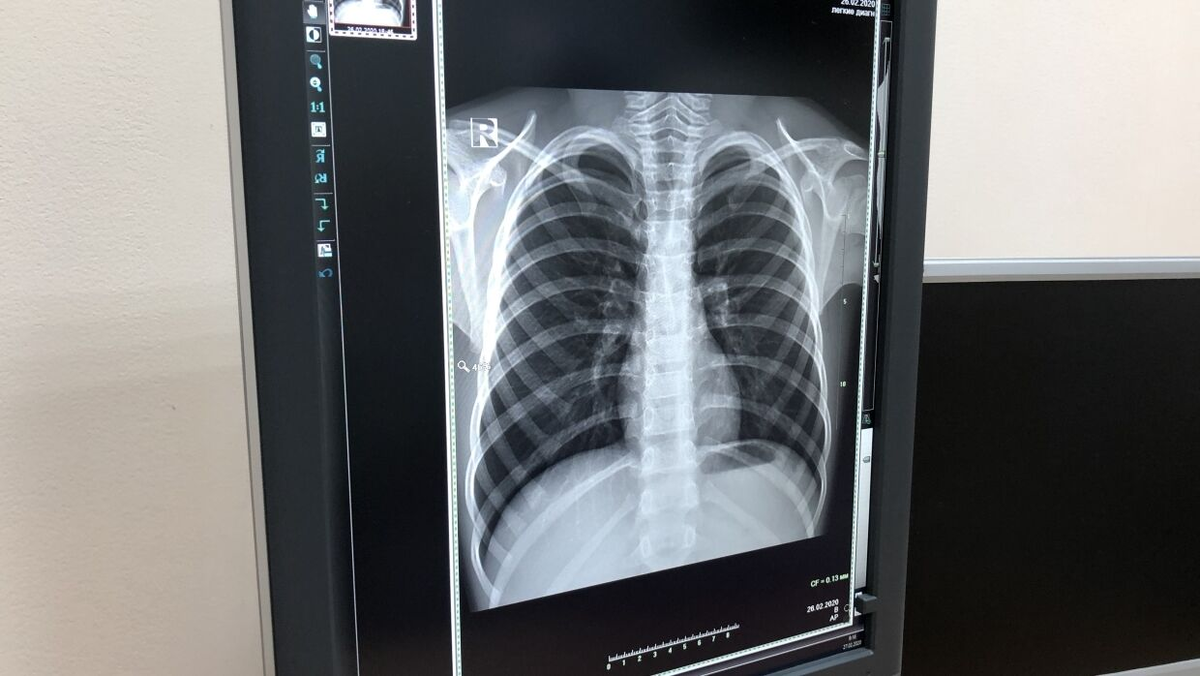

Одним из симптомов, указывающих на поражение легких и пневмонию вирусного генеза, является эффект матового стекла в легких у взрослых, определяемый по данным КТ. Но важно понимать, что это признак не только коронавируса. Пандемия COVID-19 ввела в оборот врачей новые термины, которые ранее не были знакомы пациентам. Так, при описании рентгенограмм, полученных после компьютерной томографии легких, врачи обратили внимание на одну особенность - эффект матового стекла, возникающий в ткани легких, пораженных воспалением. Но что это такое и насколько опасен подобный эффект, что он значит для пациента и врача? Эффект матового стекла в легких у взрослых Этот термин относится к расплывчатому узору с белыми крапинками, наблюдаемому на КТ легких, что свидетельствует об их повышенной плотности. Этот эффект не такой плотный, как узор "булыжной мостовой" (тоже типичный для пневмоний), и который выглядит как мозаика или брусчатка и не такой, как при типичных микробных пневмониях. По сути, «эффект мат

Этот термин относится к расплывчатому узору с белыми крапинками, наблюдаемому на КТ легких, что свидетельствует об их повышенной плотности. Этот эффект не такой плотный, как узор "булыжной мостовой" (тоже типичный для пневмоний), и который выглядит как мозаика или брусчатка и не такой, как при типичных микробных пневмониях. По сути, «эффект матового стекла» описывает «оттенки серого» между обычным сканированием легкого и сканированием крайне больного легкого, которое почти полностью белое, потому что оно полно гноя или жидкости.

Рентгенологи часто видят матовое стекло на снимках грудной клетки. Участки бывают разных форм, размеров, количества и местоположения, и они могут указывать на множество различных основных патологий, включая коронавирус и другие вирусные инфекции, хронические заболевания легких, фиброз, другие воспалительные состояния и рак. Для установления диагноза помимо описания КТ легких нужны еще и клинические симптомы, данные обследований.

Помутнение или эффект матового стекла - это описательный термин, относящийся к области повышенного затемнения в легких на компьютерной томографии (КТ) с сохраненными отметками бронхов и сосудов. Это неспецифический признак воспаления с широкой этиологией, включая инфекции, хронические интерстициальные заболевания и острые альвеолярные поражения. Помутнение по типу матового стекла также используется в рентгенографии грудной клетки для обозначения области мутной рентгеноконтрастности легких, часто довольно диффузной, в которой края легочных сосудов трудно различить.